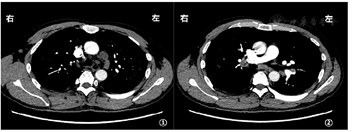

血气分析示:pH值7.394,PaO2:71.2 mmHg,PaCO2:40.1 mmHg,HCO3-:24 mmol/L;血白细胞:13.40×109/L,以淋巴细胞增加为主[中性粒细胞5.5×109/L(0.410),淋巴细胞6.5×109/L(0.485)],血红蛋白137 g/L,血小板288×109/L。肝肾功能、二便常规、凝血功能及D-二聚体未见异常;乳酸脱氢酶(LDH)164.3 U/L;红细胞沉降率97 mm/1 h,C反应蛋白0.87 mg/dL;其余感染相关抽血指标(降钙素原、血EB病毒DNA、T-Spot、G试验、GM试验均阴性;痰细菌学相关指标(细菌、真菌涂片及培养,抗酸杆菌涂片及结核杆菌DNA)均阴性;血肿瘤指标提示:CA125增高(77.5 U/mL),其余神经元特异性烯醇化酶(NSE)、癌胚抗原、CA153、TPS、FPSA均阴性;抗核抗体增高,效价为1∶100(核颗粒型);抗核抗体谱抗组蛋白抗体弱阳性,余项均阴性;ASO、类风湿因子、血管炎指标均阴性;血IgM 12.2 g/L、补体C3:0.735 g/L、补体C4:0.114g/L,IgG、IgA均正常范围内;免疫固定电泳显示免疫球蛋白Kappa弱阳性、IgM弱阳性,IgG、IgA及Lamda均阴性;血清蛋白电泳:白蛋白为47.8%、γ-球蛋白为28.1%;2020年12月1日胸部CT(图1,图2)提示双肺多发实性小结节影(大小3~5 mm),双侧胸腔少量积液,纵隔多发增大淋巴结,肺动脉造影未见异常。

超声提示胸腔积液量少未能定位穿刺;浅表淋巴结彩超:双腹股沟及双颈部多发肿大淋巴结,最大约7~9 mm×15~19 mm,双侧腋窝超声未见肿大;经外科评估无法淋巴结活检。心脏彩超无异常,腹部彩超提示肝脾不大,余无异常。正电子发射计算机断层扫描(PET-CT):两肺门、纵隔、肝门区、腹膜后多发淋巴结增大,最大者14 mm×18 mm,SUVmax:10.1。双侧胸膜增厚,右侧胸膜多发小结节,双侧胸腔少量积液。